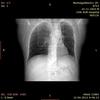

Уважаемые специалисты! Благодарю Вас за Ваши бесценные отзывы и комментарии. В продолжение темы http://www.radiomed.ru/cases/kt-emfizema хотел бы проконсультироваться относительно последнего снимка, который был получен сегодня.

Результаты последней компьютерной томографии от 07.03.2014г.

На серии МСКТ и MPR изображений в легочном и мягкотканном окне объем левого легкого уменьшен, в верхней доле левого легкого определяется гигантская булла с толстыми стенками размером 45-124 мм, занимающая всю верхнюю долю ("синдром исчезающего легкого"). Вдоль культи верхнедолевого бронха левого легкого отмечаются послеоперационные танталовые швы. Корень левого легкого подтянут вверху. Очаговых и инфильтративных изменений в легких не определяется. Просвет трахеи, главных и долевых бронхов прослеживаются, стенки бронхов утолщены и деформированы. Внутригрудные лимфатические узлы не увеличены. Диафрагма расположена обычно, контуры ровные, четкие. Сердце обычно расположено и имеет правильную конфигурацию. Камеры сердца не увеличены.

Заключение: Состояние после лобэктомии слева. Эмфизема верхней доли левого легкого с гигантской буллой.

Не уверен, но кажется, что есть отрицательная динамика. ИМХО, исследование всегда лежа, так вот в оной булле, что-то накапливается, на саггиталах сзади, типа жидкости.( от 7.03.2014г.)smiley Ну подождем эмпиемы.

Вы правы, алкс, явный уровень жидкости. Таким образом, пневмоторакс уже осложненный.